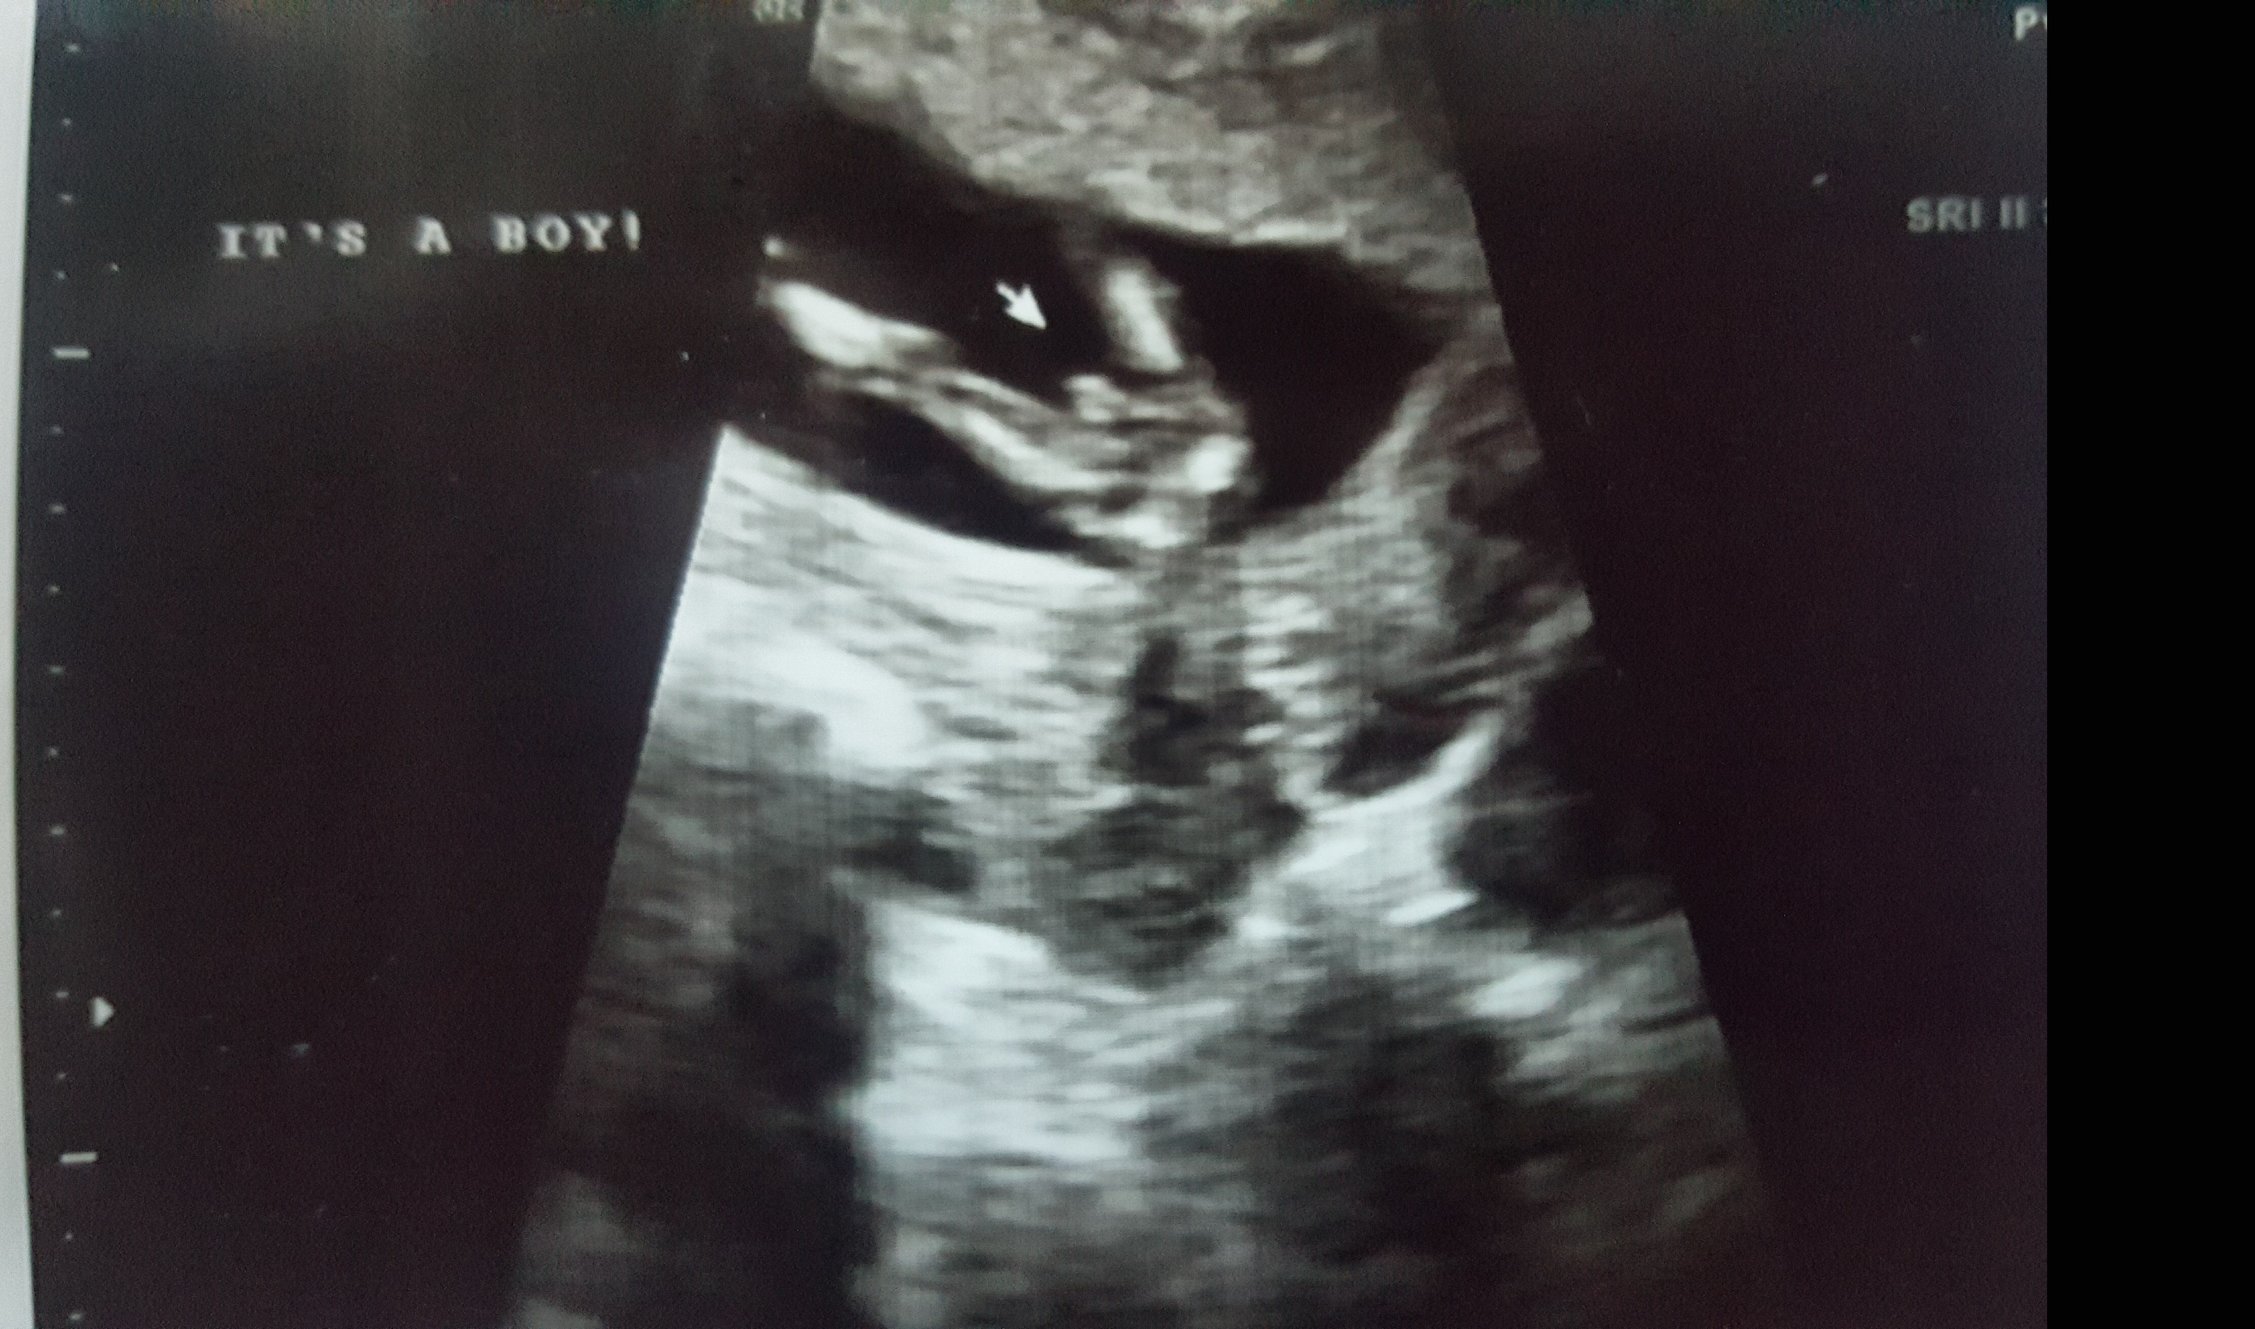

I am 13w2d today and my baby boy is measuring 6 days ahead so 14wks. They said I am not further along just bc baby is so idk how that all works. My due date is March 15th. I had the NT 2wks after the appt where I did Harmony. Neck measured 1.7mm. Here is scan from NT on Sept 1: